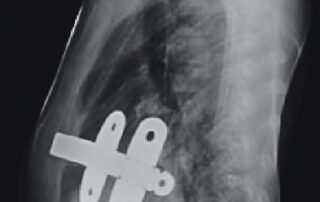

During the Nuss procedure, Dr Schewitz will make two small incisions in the side of the chest. A stainless steel bar is then inserted behind the deformed breastbone and attached the outer edge of the ribs. The bar will then be turned to raise the breastbone. This bar is left in place to raise the breastbone and correct the deformity over 3 years. The bar is then removed.